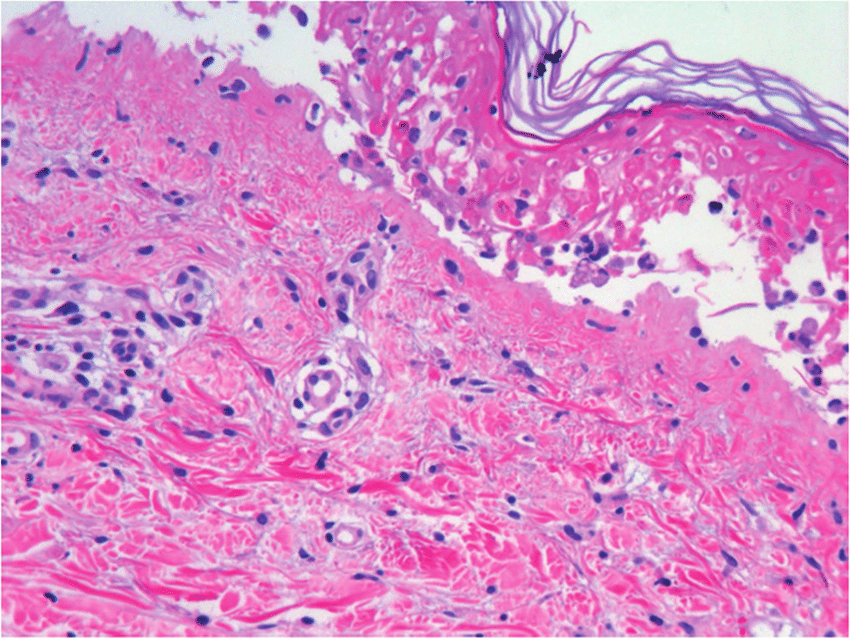

Necrólisis Epidérmica Tóxica: Revisión Clínica y Terapéutica

En general, su etiología y presentación son consensuadas, definiéndose como una necrólisis generalizada de la epidermis que se produce como una respuesta inmune descontrolada a un fármaco específico o a uno de sus metabolitos, destacando el cotrimoxazol y el alopurinol como los más importantes. Esta necrólisis conduce a un desprendimiento masivo de la capa epidérmica de la piel, con mayor incidencia en el torso, miembros superiores y cara. Eur. Burn J. 8 agosto 2022